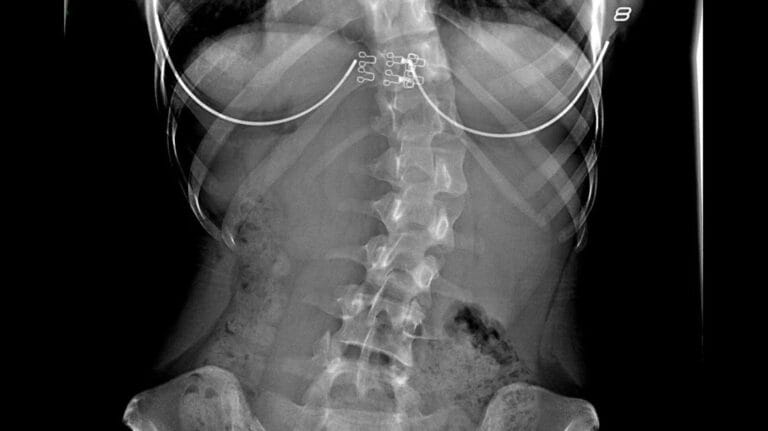

Slip disc, atau lebih dikenali sebagai hernia diskus, berlaku apabila nucleus pulposus — bahan gel yang lembut di tengah-tengah disk tulang belakang — terkeluar dari lokasinya yang normal. Bayangkan disk tulang belakang anda seperti sebuah donut dengan jem di dalamnya. Kadang-kadang, jem itu boleh ‘terkeluar’ dan mula memberi tekanan pada saraf sekeliling.

Slip disc berlaku apabila nucleus pulposus terkeluar dari lokasi normal di dalam disk tulang belakang. Bayangkan salah satu cakera dalam tulang belakang anda "tergelincir" sedikit dari tempat biasa. Ini boleh menyebabkan saraf berdekatan tertekan.